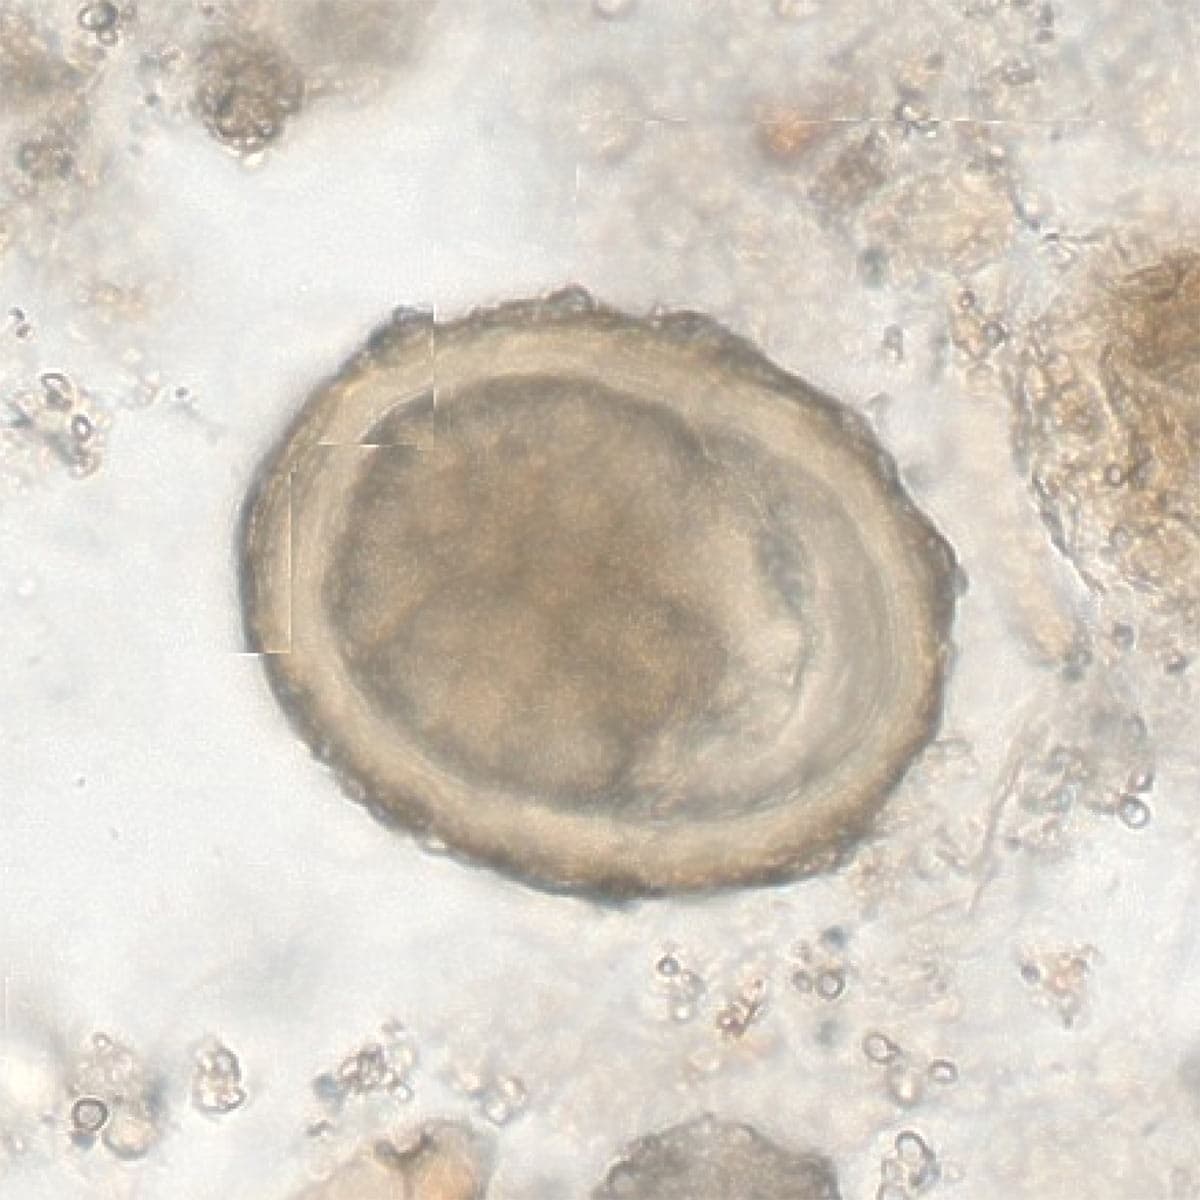

Automatic detection of rare species

Built on worldwide parasite-positive specimens, ParaScout AI identifies a vast number of parasite species, including those that are clinically rare or challenging to find.